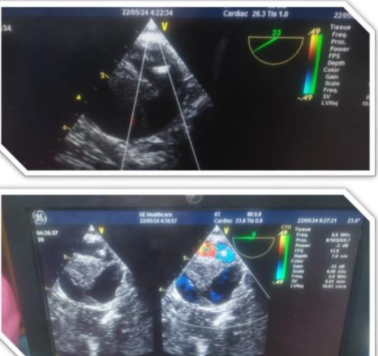

وأوضح بيان هيئة الرعاية الصحية، التدخل الجراحي تم على مرحلتين لمريض يبلغ من العمر 44 عامًا كان يعاني من انسلاخ بالشريان الأورطي النازل وتقرحات بقوس الشريان الأورطي وتجمع دموي بالشريان الأورطي الصاعد، حيث وصل المريض إلى قسم الطوارئ بالمستشفى في حالة حرجة يعاني من آلام شديدة بالصدر والظهر وارتفاع في ضغط الدم، وعلى الفور تم التعامل معه وإجراء الفحوصات اللازمة، ونقله للعناية المركزة للسيطرة على حالته ومنع تدهورها.

وتابع البيان، بناءً على التقييم الطبي للحالة تقرر إجراء تدخل مزدوج حيث تضمنت المرحلة الأولى إجراء عملية قلب مفتوح لاستبدال الشريان الأورطي الصاعد وإعادة توصيل شرايين الرقبة باستخدام شرايين صناعية، فيما شملت المرحلة الثانية تركيب دعامات مغطاة بالشريان الأورطي وقوسه باستخدام تقنية TEVAR وغلق الشريان تحت الترقوة باستخدام سدادة عبر القسطرة التداخلية تحت توجيه الأشعة التلفزيونية عن طريق المريء وتم تنفيذ التدخلين باستخدام أحدث التقنيات الطبية وبكفاءة عالية أسفرت عن تحسن ملحوظ في حالة المريض الذي غادر المستشفى بعد أسبوع من المتابعة الدقيقة وهو بحالة مستقرة الآن.

هذا، وقد تم إجراء العملية على يد نخبة من الكوادر الطبية بمستشفى طيبة التخصصي التابع للهيئة شملت كل من الدكتور محمد أبو منصور استشاري ورئيس قسم جراحة الأوعية الدموية والدكتور محمد عبد القادر استشاري ورئيس قسم جراحة القلب والصدر والدكتور سعيد عبد العزيز أستاذ جراحة القلب والصدر بطب القصر العيني والدكتور أحمد الجندي والدكتور شادي مجلي استشاريي جراحة الأوعية الدموية والدكتور محمد السيد استشاري أمراض القلب منفذ إيكو المريء والدكتورة سارة منصور والدكتور محمد شوقي مبروك استشاريي التخدير والدكتور محمد خميس والدكتور هيثم جميل استشاريي العناية المركزة، و بمعاونة فريق التمريض المتميز بالمستشفى في تناغم كامل يجسد جاهزية البنية التحتية والكفاءات البشرية المؤهلة داخل منشآت الهيئة للتعامل مع الحالات الدقيقة والمعقدة.